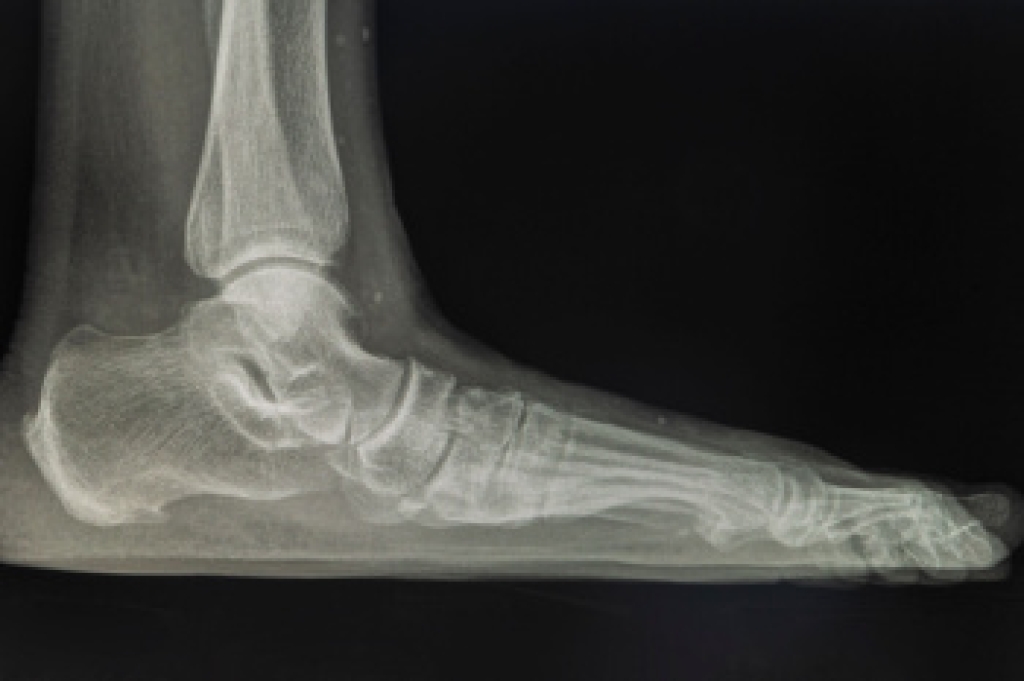

To figure out the cause of foot pain, podiatrists utilize several different methods. This can range from simple visual inspections and sensation tests to X-rays and MRI scans. Prior medical history, family medical history, and any recent physical traumatic events will all be taken into consideration for a proper diagnosis.